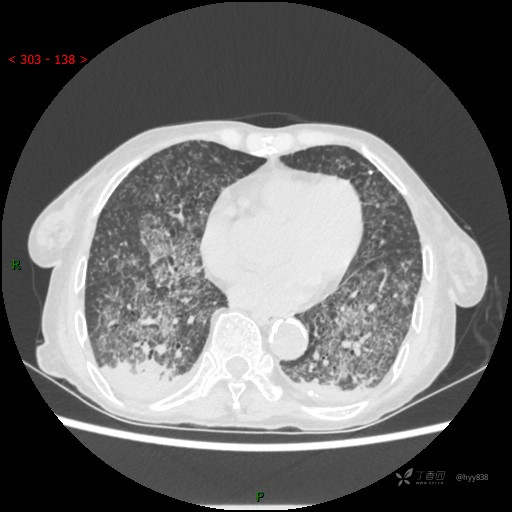

肺部弥漫性、疑难病变,感染或肿瘤?一元论或二元论?贴贴精彩---结果公布~

简要病史:患者10余天劳累后出现发热,最高体温达39.5℃,无畏寒、寒战、鼻塞、流涕,无头晕、头痛,无心慌、胸闷、胸痛,无咳嗽、咳痰、气喘,无反酸、烧心、恶心呕吐,无腹痛、腹胀等不适,于2022-5-31至当地中医医院住院治疗,诊断为重症肺炎,予以抗感染、抗病毒等对症支持治疗,仍反复发热,现为求进一步诊治,至我院门诊就诊,门诊以“重症肺炎”收入我科。 起病以来,患者精神、饮食、睡眠差,大小便正常,体力下降,体重无明显变化。

临床诊断:重症肺炎

胸部CT平扫